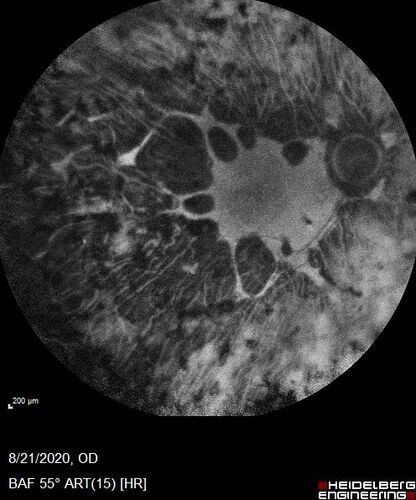

67 year old female with diabetes since age 8.  She had heavy PRP laser to both eyes in the 1970s by Lloyd M. Aiello, M.D, the father of PRP laser.  Her vision is poor now, 1/200 OD and 20/200 OS.

Pan Retinal Laser from original DRS study in the 1970s - 50 years later